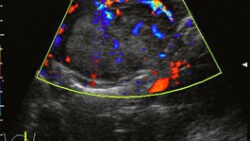

腎血管筋脂肪腫

疾患腎血管筋脂肪腫:・血管周囲類上皮細胞(perivascular epithelioid cell: PEC)に由来する腫瘍(PEComa)として分類される・血管、平滑筋、脂肪組織よりなる。・ほとんどが良性腫瘍だが、ごく稀に悪性化した報告...